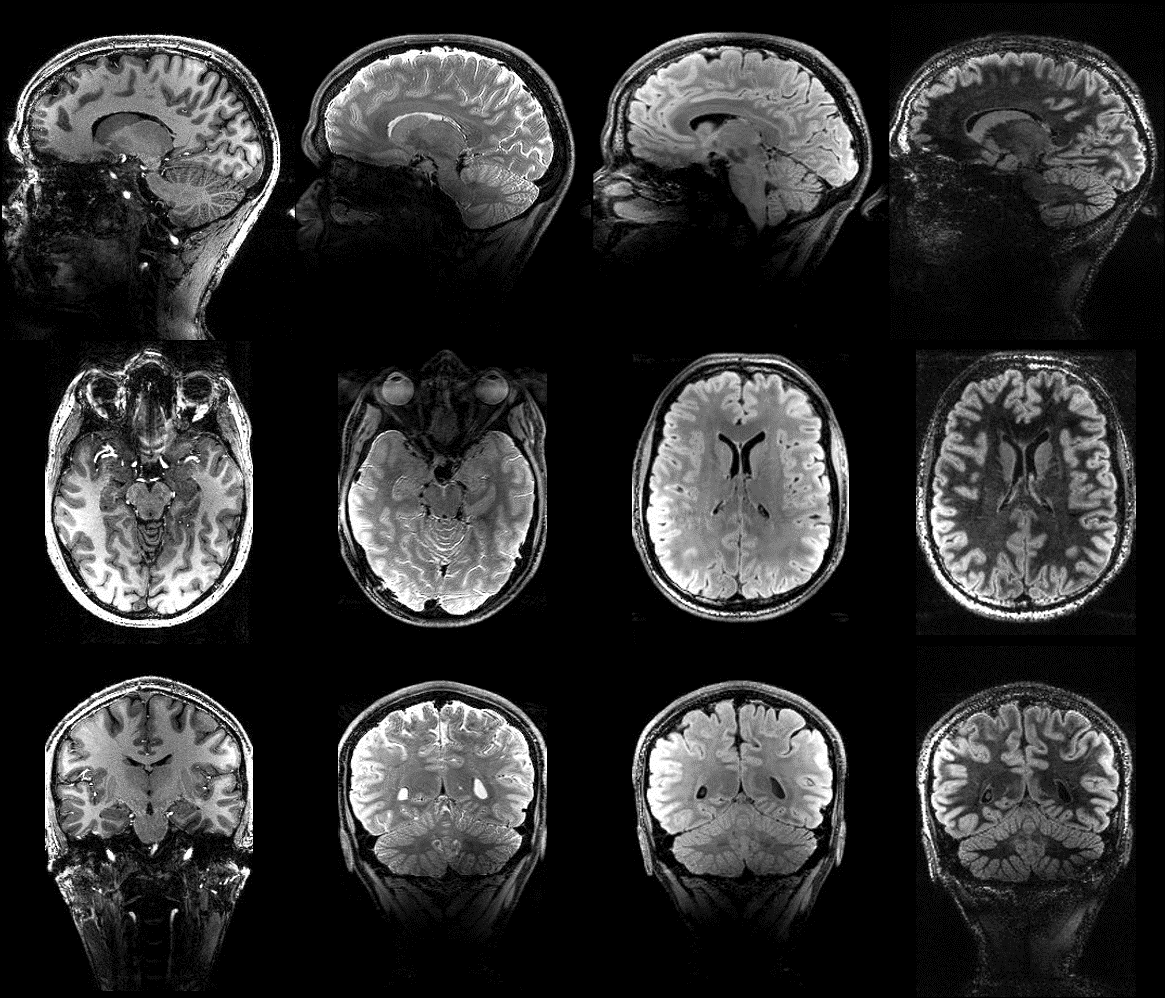

We are very proud to release the new version of our PASTeUR package for Magnetom Terra systems. Our goal is to bring calibration free parallel transmission solutions with homogeneous excitation throughout the brain using the Nova 8Tx/32Rx coil. We are willing to share the package with other clinical research laboratories and evaluate the potential benefit for the clinic.

At the moment, the package contains a set of 3D non selective sequences. However, we are working on expanding it with slab selective 3D acquisitions as well as 2D sequences.

Research interests

- Parallel transmission at 7T : We developped a package of 3D anatomical sequences that integrate the so-called Universal Pulses to bring pTx closer to the clinic. These sequences do not need calibration scans nor pulse design pre-processing and manage to homogenize the signal throughout the brain. Sequences available within this package are : 3D-GRE, MPRAGE, MP2RAGE, T2w-SPACE, FLAIR, DIR. This package is available for classic Siemens 7T (VB17 software) as well as for Terra systems on C2P request.

Universal Pulses Enable A One-Hour Clinical Neuroimaging Protocol At Submillimeter Resolution On The NextGen 7T

Pushing The Image Quality By Integrating FatNav And PTx Universal Pulses In MPRAGE And MP2RAGE Sequences At 7T

Proceedings of the ISMRM 2024, Singapore, p4895.